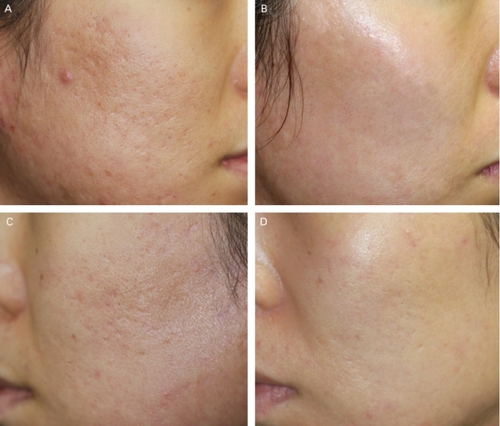

作為治療工具的PRP並不是只想消除疼痛時應該使用的東西。相反的,PRP的功能遠多於消除疼痛,包含傷口癒合、逆轉皮膚衰老、除皺、乾眼症、神經再生、骨頭結合與再生、甚至女性私密處注射。